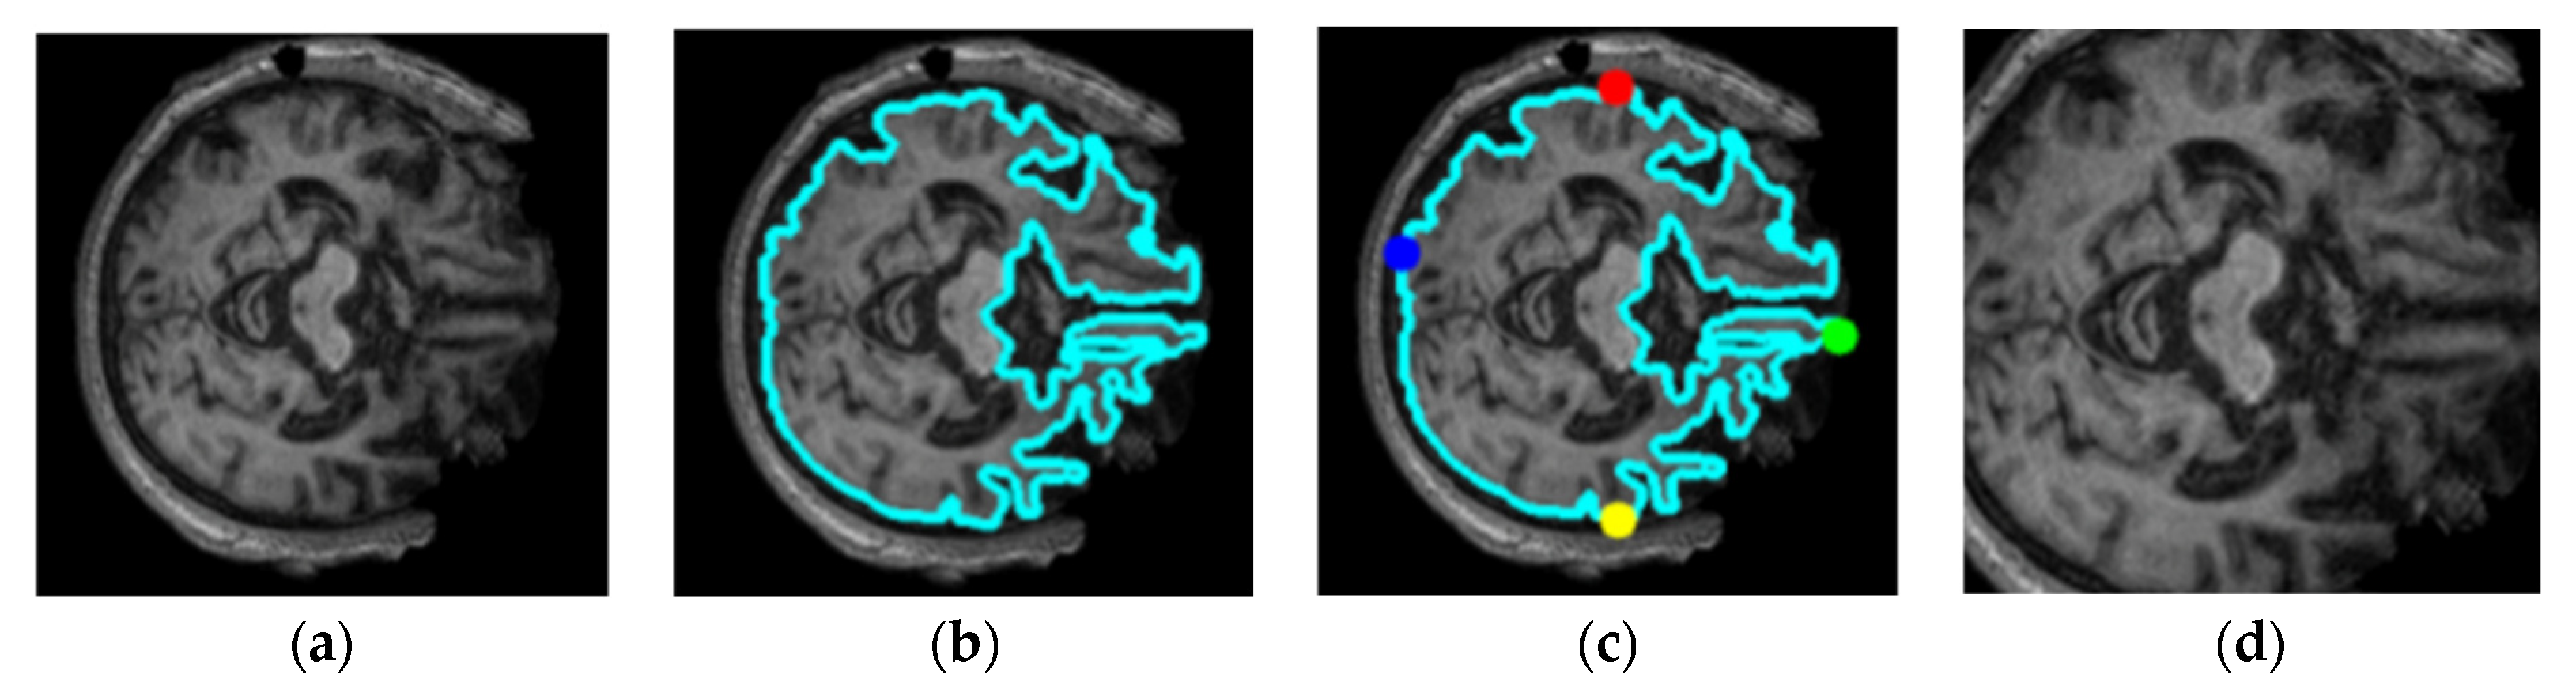

- This paper conducts a qualitative evaluation in the result variations of pre-trained models between cropping and without cropping of MRI images.

3.1. Dataset Pre-Processing

4.4. Visualizations